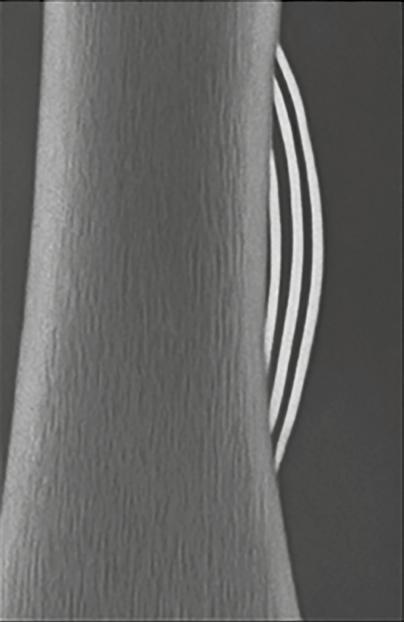

Se refiere al límite entre el hueso sano y la lesión. Una transición bien definida suele asociarse con lesiones benignas, mientras que los márgenes mal definidos tienden a sugerir comportamiento agresivo o maligno. Para interpretar correctamente una lesión osteolítica, uno de los aspectos clave es evaluar la zona de transición entre la lesión y el hueso sano circundante. Esta zona actúa como un indicador fundamental para diferenciar entre procesos benignos y malignos. Las lesiones bien definidas, con bordes nítidos y una transición estrecha, suelen indicar un crecimiento lento y comportamiento biológico no agresivo. En algunos casos, incluso se puede observar un borde esclerótico, lo que refuerza la idea de una lesión inactiva. Sin embargo, en pacientes mayores de 30 años, y especialmente en mayores de 40, no se puede descartar la posibilidad de metástasis o plasmocitoma, incluso si las imágenes sugieren benignidad. En la Figura 2 , por ejemplo, se muestran tres lesiones con zona de transición estrecha en pacientes pediátricos, cuyas placas de crecimiento aún no se han cerrado, lo cual refuerza el diagnóstico de lesiones benignas.

Figura 2. Zona estrecha de transición. 1. Fibroma no osificante. 2. Quiste óseo simple. 3. Quiste óseo aneurismático. Tomada de: Jan van der Woude R, Smithuis R. Bone tumors. Differential diagnosis [Internet]. 2010 [consultado 2025 oct 13]. Disponible en: https://radiologyassistant.nl/ musculoskeletal/bone-tumors/differential-diagnosis